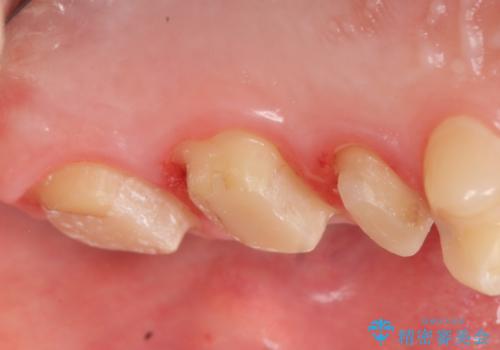

- 左上の歯が痛くてものが咬めないといらっしゃった方の症例です。

左上6は自発痛および持続痛を認めたため根管治療後、オールセラミッククラウンによる補綴を行いました。

左上7は冷水痛のみだったため、慎重に虫歯の除去を行い症状がないことを確認後、オールセラミッククラウンによる補綴を行いました。

左上5は再根管治療後、オールセラミッククラウンによる補綴を行いました。

- オールセラミッククラウン…¥100,000×3、仮歯…¥10,000×3、ファイバーコア…¥20,000×2費用は治療当時の料金となります